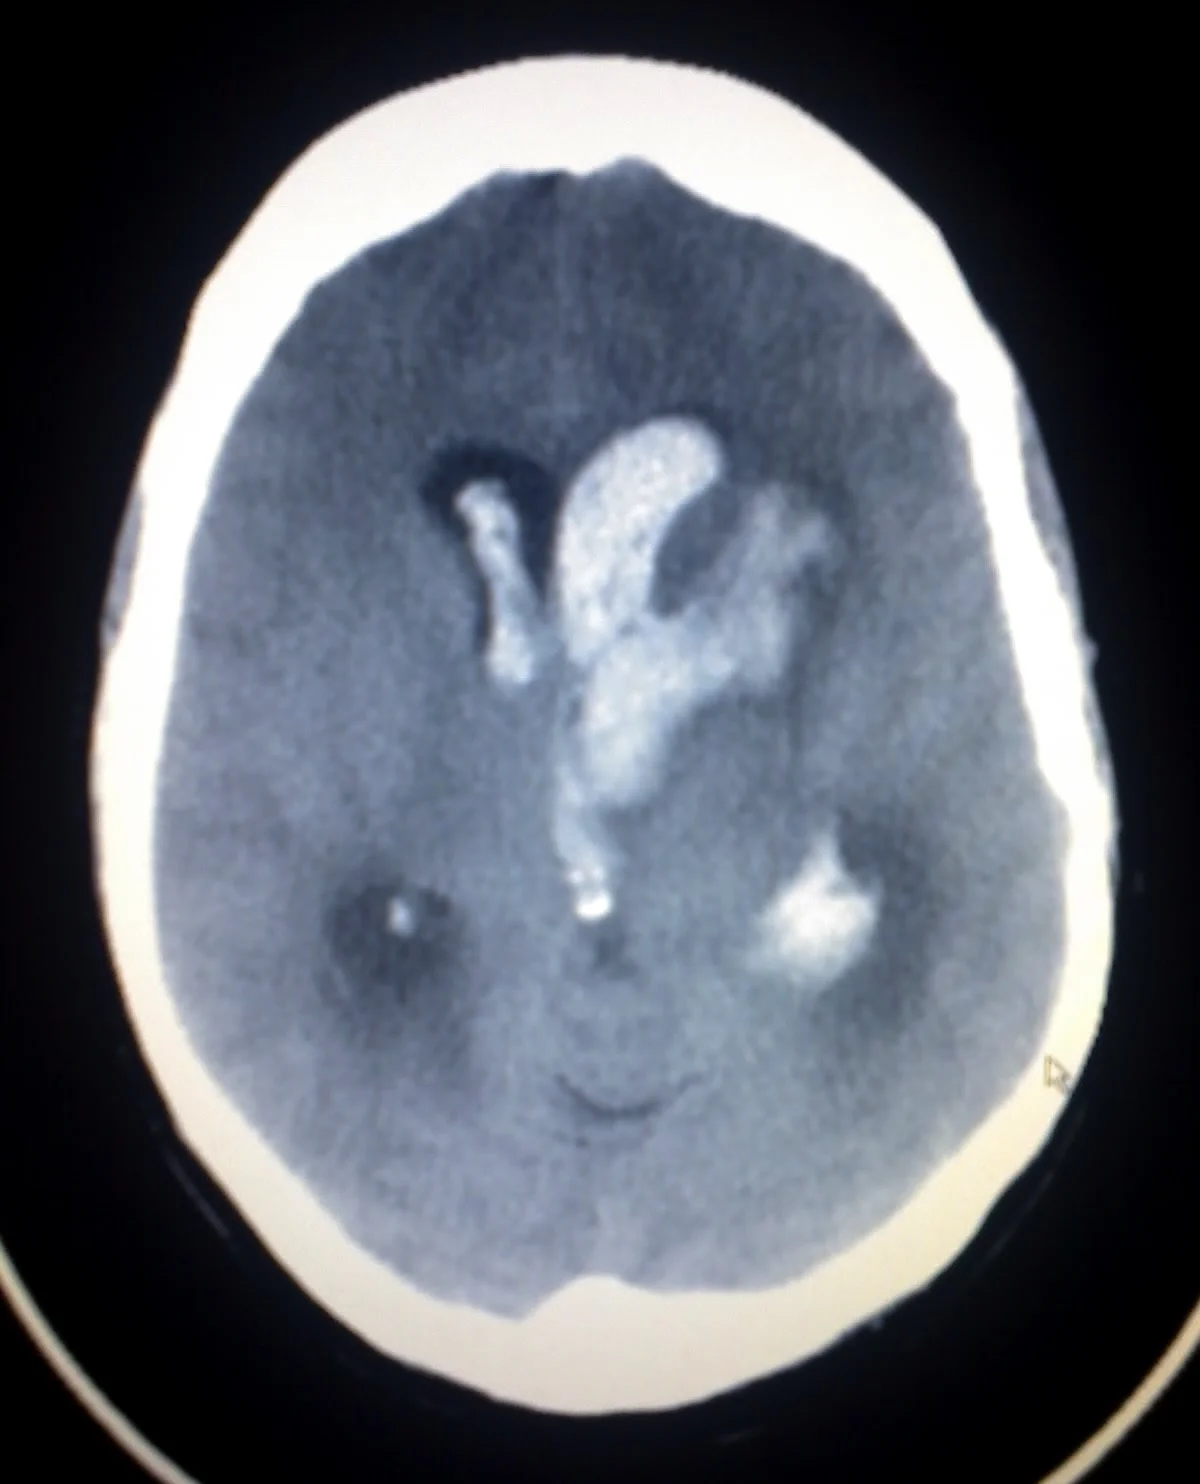

/As 2016 comes to a close, Dr. McKean taught us about transfusion related lung injury, PEs, TCA overdoses, and the use of platelets in ICH during M&M. We learned the basics about the renal panel with Dr. Owens. Drs. Betz and Summers battled it out over drug-induced hepatitis and Dr. McKee taught us about Crypococcal Meningitis in her case follow-up. The year wrapped up with another Levy Cup Pre-season battle lead by Drs. Boyer and Winders.